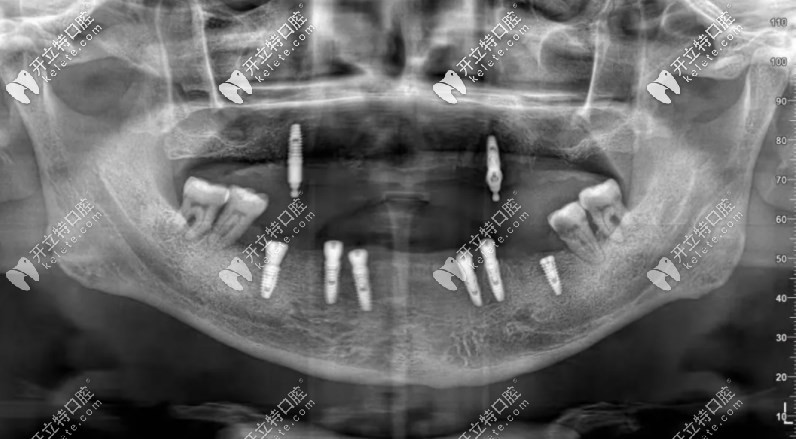

下圖是李叔叔種完牙拍的片子▼

確定是植入了8顆種植體,品牌是德國camlog。